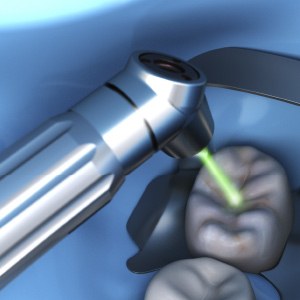

All-Tissue Laser Dentistry: How This Breakthrough Technology Delivers on Its Promise

Monday, February 18, 2019

With anesthesia-free, blood-free, and suture-free procedures, laser dentistry is a true breakthrough that delivers a completely different experience. In this eBook, four clinicians explain in detail how laser dentistry has impacted their practice and patient care.

Lasers in Dentistry and Dental Hygiene

Wednesday, December 19, 2018

Lasers are frequently used in dentistry and changing the way many clinicians practice dentistry today. This article will briefly examine the history and fundamentals of lasers, essential safety information, and how lasers are used in dentistry and dental hygiene.